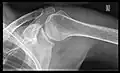

X-ray

Projectional radiography views of the shoulder include:

- AP-projection 40° posterior oblique after Grashey

The body has to be rotated about 30 to 45 degrees towards the shoulder to be imaged, and the standing or sitting patient lets the arm hang. This method reveals the joint gap and the vertical alignment towards the socket.[26]

-

CR. shoulay film. -

Transaxillary conventional radiography -

Y-projection conventional radiography